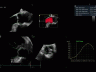

• Автоматическая оценка регионарной сократимости миокарда левого желудочка с расчетом большой группы параметров с помощью функции Automated Function Imaging (AFI).

• Протоколы AFI Stress, позволяющие получать стандартные апикальные проекции в двумерном режиме и рассчитывать регионарную и глобальную продольную деформацию миокарда на всех уровнях нагрузки.

• Функция 4D Strain для расчета глобальной и регионарной деформации миокарда на основе алгоритма пространственного спекл-трекинга, отображаемая в виде диаграммы «бычий глаз».